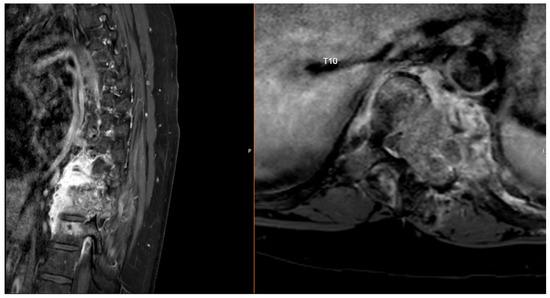

He underwent intensity-modulated radiation therapy (IMRT) using volumetric modulated arc therapy (VMAT) over 1 year ago, receiving 5040 cGy to the soft tissue component and 4760 cGy to the osseous component. Although the neoplastic viability of the surrounding osseous component remained uncertain, it was decided to include it in the radiation dose field to address all suspected tissue as at risk. Furthermore, due to the spinal hardware from surgery, the tumor margins, tumor volume, and location of the spinal cord were difficult to delineate, posing a further challenge in radiation planning. This treatment also took into consideration adjacent structures including the lungs, spinal cord, bowels, and kidneys (Figure 4 and Figure 5).

Figure 4. Dosimetry illustrating tumor dose, and dose–volume histogram of tumor (royal blue) and adjacent organs at risk such as spinal cord (brown), right and left lungs (white), and kidneys (gold and green).

Figure 5. Dose cloud picture illustrating IMRT coverage of the target volume using VMAT. Planning accounts for hardware artifacts and proximity to critical structures such as bowel, liver, heart, and kidneys.

In this case, the extensive tumor involvement made complete resection too risky, so spine stabilization and prevention of neurologic catastrophe were the primary goals. Progression of unresected disease on serial imaging and history of two previous spinal procedures made a third resection too risky and unlikely to remove all viable tumors. As a result, treatment pivoted to non-surgical options. Immunohistochemical staining for FOS gene rearrangements, which are only present in osteoid osteoma and osteoblastoma, can be useful in narrowing the diagnosis [7]. However, these mutations are absent in a minority of cases, which necessitates the usage of other diagnostic tools such as radiologic and histologic features [7]. Additionally, while less relevant today, serum alkaline phosphatase can aid in differentiating conventional and aggressive variants of osteoblastoma, which could have proved useful in this case [2]. Irrespective of the diagnosis, the multilevel vertebral involvement mandated a large-scale intervention aiming to reduce tumor burden and stabilize the spine. Radiotherapy offers a noninvasive option when surgery is not feasible [19]. Radiotherapy has also been utilized in larger single-institution reports with a range of doses of 50–70 Gy in standard 1.8–2.0 Gy fractions, which also controlled tumor progression at lower doses [20]. Intensity-modulated radiation therapy (IMRT) allows for conformality of radiation dose to tumor target tissue while maximally sparing dose to adjacent organs. This was key for this patient with tumors surrounding important neurovascular structures and viscera. This case carried further complexities, including implantation of surgical hardware which reduced precision in locating the encased spinal cord, and the uncertainty of needing to include the surrounding osteoid component of the tumor in the treatment volume. To account for these challenges, the radiation dose was customized to provide maximum dose to the osteoblasts within the soft tissue component surrounding the spinal cord while retaining safety for cord tolerance (50.4 Gy), and a lower but sterilizing dose to any microscopic deposits of viable cells within the osseous surrounding component (47.6 Gy). This lower dose allowed tolerable dosing to adjacent radiosensitive organs including the lungs, kidneys, and bowel at standard fraction sizes. In this case, the patient remains free from subacute and moderate-term radiation toxicity.